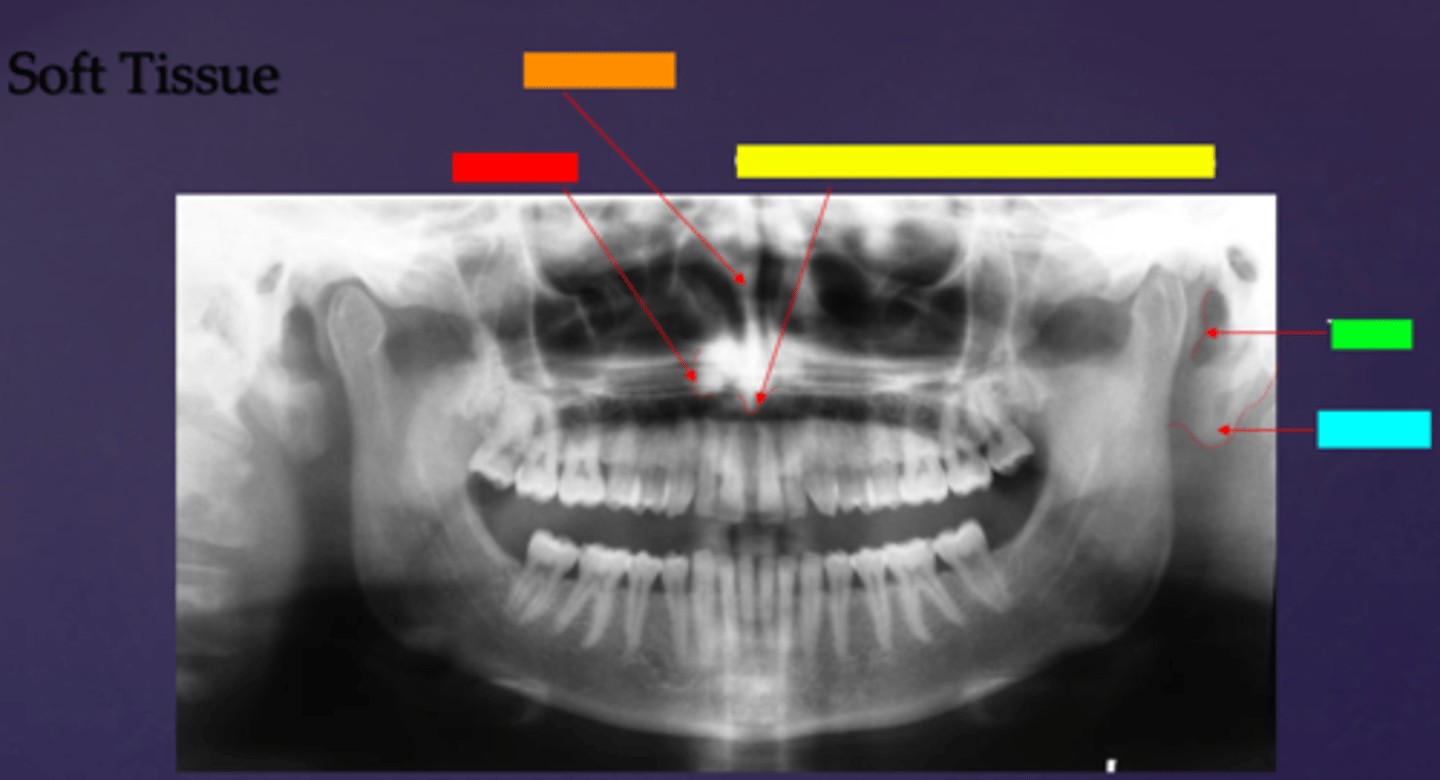

ID the soft tissue anatomy indicated by the arrow pointing from the hot pink box:

inferior nasal concha (turbinate)

ID the soft tissue anatomy indicated by the arrow pointing from the brown box:

upper lip

ID the soft tissue anatomy indicated by the arrow pointing from the white box:

lower lip

ID the soft tissue anatomy indicated by the arrow pointing from the grey box:

ghost image of opposite mandible